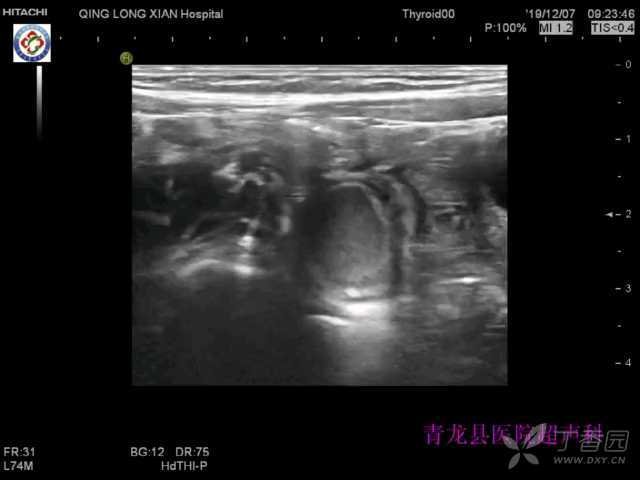

1岁小儿,超声检查发现右下腹囊性回声,与肠管关系密切。

囊肿型:又分为腔外型和腔内型。腔外型:表现为紧邻肠管的圆形或类圆形囊肿,边界清晰,内壁光整。壁偏厚,厚度约2mm,可探及肌层结构,类似消化道壁结构。囊液较清亮,囊内无分隔。小的囊肿可继发肠套叠,在套入头端可见囊腔回声。十二指肠重复多为十二指肠降部旁的囊肿型。腔内型:在重复畸形病例中腔内型是较少见类型,多在婴幼儿期发现,多造成肠梗阻。好发于回盲部,回盲部肠腔内见囊肿,并见近段肠管异常积液扩张。